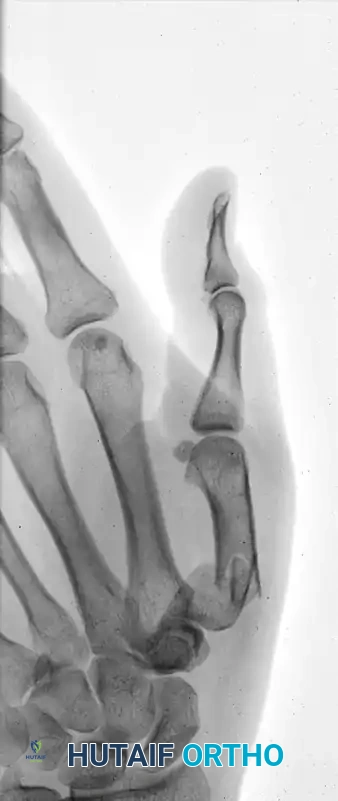

The following sequence illustrates the progression from injury to successful closed reduction and K-wire fixation into the trapezium: